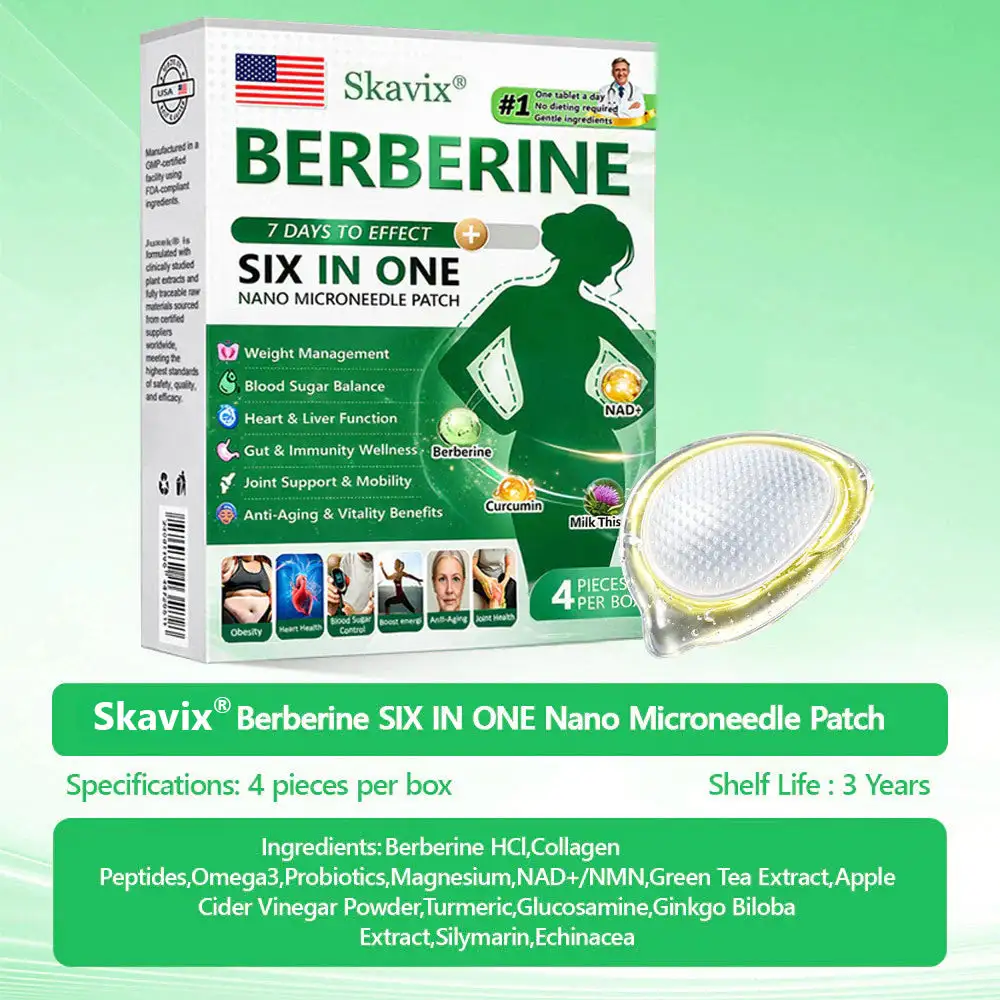

Powerful Ingredients, Proven Results

Supports natural cellular balance and helps maintain overall body wellness.

Post-Weight Loss Skin Care:

After rapid weight loss, skin often becomes loose, saggy, and less elastic.

Skavix® has specially addedCollagen Peptidesand collagen-boosting factors to the formula. These key ingredients stimulate collagen and elastin synthesis, helping the skin regain firmness and thickness. They also smooth fine lines, reduce sagging, and restore a youthful, healthy glow. This ensures you not only lose weight successfully but also maintain a toned, youthful physique—avoiding the problem of “looking older after slimming down.”Weight loss and rejuvenation are achieved simultaneously.